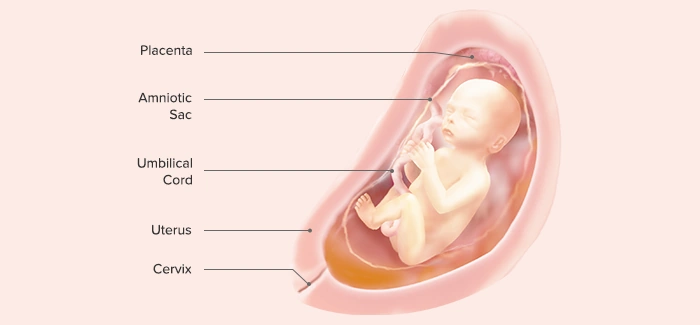

در هفته بیستوچهارم بارداری ممکن است پزشک برای بررسی رشد جنین، ارزیابی حرکات، میزان مایع آمنیوتیک و بررسی سلامت جفت برای شما سونوگرافی تجویز کند. این سونو معمولاً بخشی از «سونوگرافی رشد» محسوب میشود و به پزشک نشان میدهد که روند رشد جنین طبیعی است یا نیاز به پیگیری بیشتری دارد.

در سونوگرافی هفته ۲۴ چه مواردی بررسی میشود؟

۱) وزن و اندازه جنین

پزشک در این سونو، اندازهگیریهای زیر را انجام میدهد:

-

دور سر (HC)

-

دور شکم (AC)

-

طول استخوان ران (FL)

-

وزن تخمینی جنین (EFW)

اگر اندازهها داخل محدوده طبیعی باشند، نشاندهنده رشد مناسب است.

۴) وضعیت جفت و بند ناف

-

موقعیت جفت (قدامی، خلفی، جفت پایین)

-

بررسی ضخامت جفت

-

سلامت بند ناف و جریان خون از طریق داپلر (در صورت نیاز)

این موارد در پیشگیری از مشکلات احتمالی بسیار مهماند.

۵) میزان مایع آمنیوتیک

آمنیوتیک زیاد یا کم میتواند نشانه مشکل باشد.

پزشک با اندازهگیری AFI یا MVP (بزرگترین پاکه مایع) این موضوع را ارزیابی میکند.